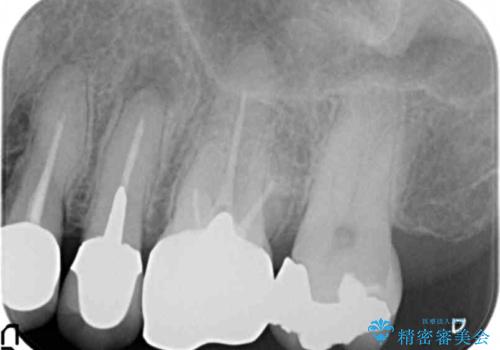

- 銀歯を白くしたいとご希望され、来院された患者様です。

他の歯科医院で銀歯をはずした時に、銀の詰め物が喉に飛んできたことがトラウマとなり、歯科治療が怖くなってしまったとのことでした。

患者様のご希望により、左上6クラウン、左上7インレーによるセラミック治療を行いました。

再根管治療はご希望されなかったため行っておりません。